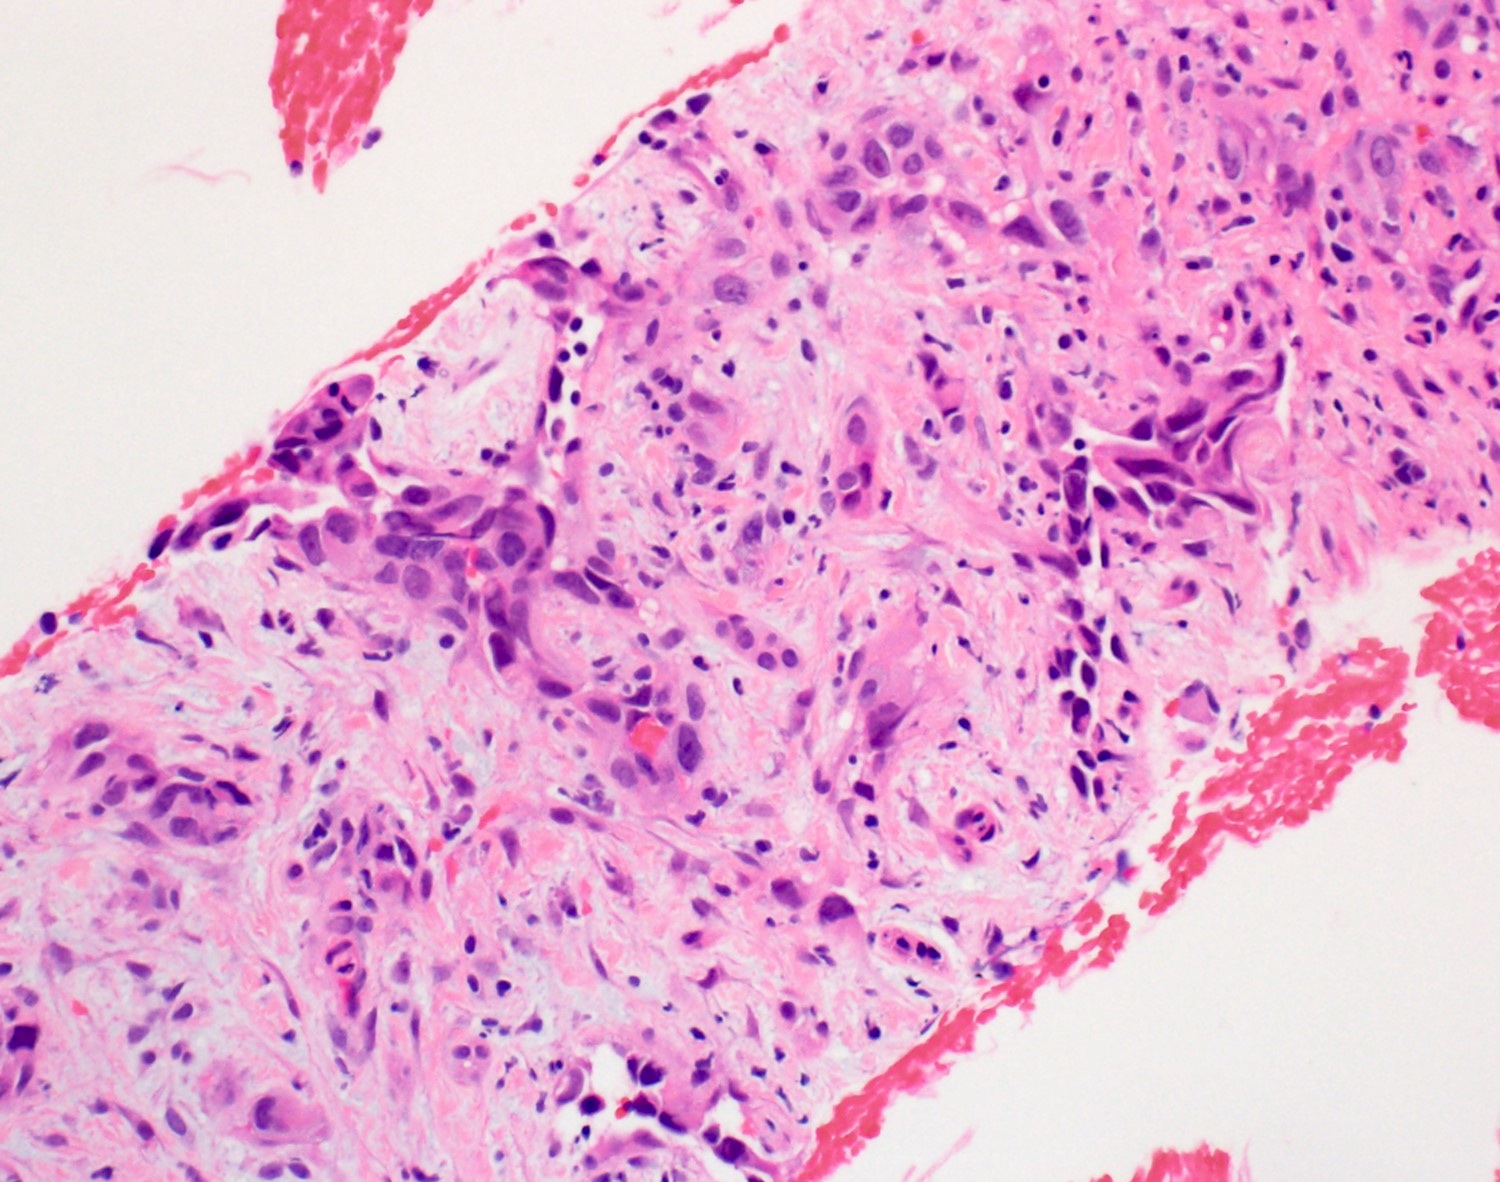

Microscopic (histologic) description

- 2 main histologic growth patterns were described (Am J Surg Pathol 2019;43:581)

- Non-mass forming

- Sinusoidal

- Dilated sinusoids lined by atypical endothelial cells seen in angiosarcoma with hyperchromatic nuclei

- Peliotic

- Blood pools and fibrin surrounded by hepatocytes

- Peripheral clusters of atypical endothelial cells seen in angiosarcoma mixed with inflammatory cells may extend into the sinusoids

- Mass forming

- Vasoformative shows architectural complexity and interconnecting vascular channels

- Anastomosing vessels and haphazard vascular channels

- Endothelial cells show tufting, atypia and mitotic figures

- Nonvasoformative shows epithelioid to spindled morphology

- Epithelioid morphology (epithelioid angiosarcoma) is most common (Am J Surg Pathol 2004;28:298)

- Solid nests or sheets of tumor cells

- Tumor often invades into sinusoids and hepatic venules at the periphery

- Cells have eosinophilic cytoplasm and oval nuclei

- Chromatin can be vesicular

- Multinucleated giant cells can be present

- Unusual growth patterns (Am J Surg Pathol 2019;43:581)

- Whorls of spindle cells in a background of chronic inflammation and loose myxoid to sclerotic stroma

- Infantile hemangioma-like angiosarcoma

- Hemangioma-like angiosarcoma

Microscopic (histologic) images